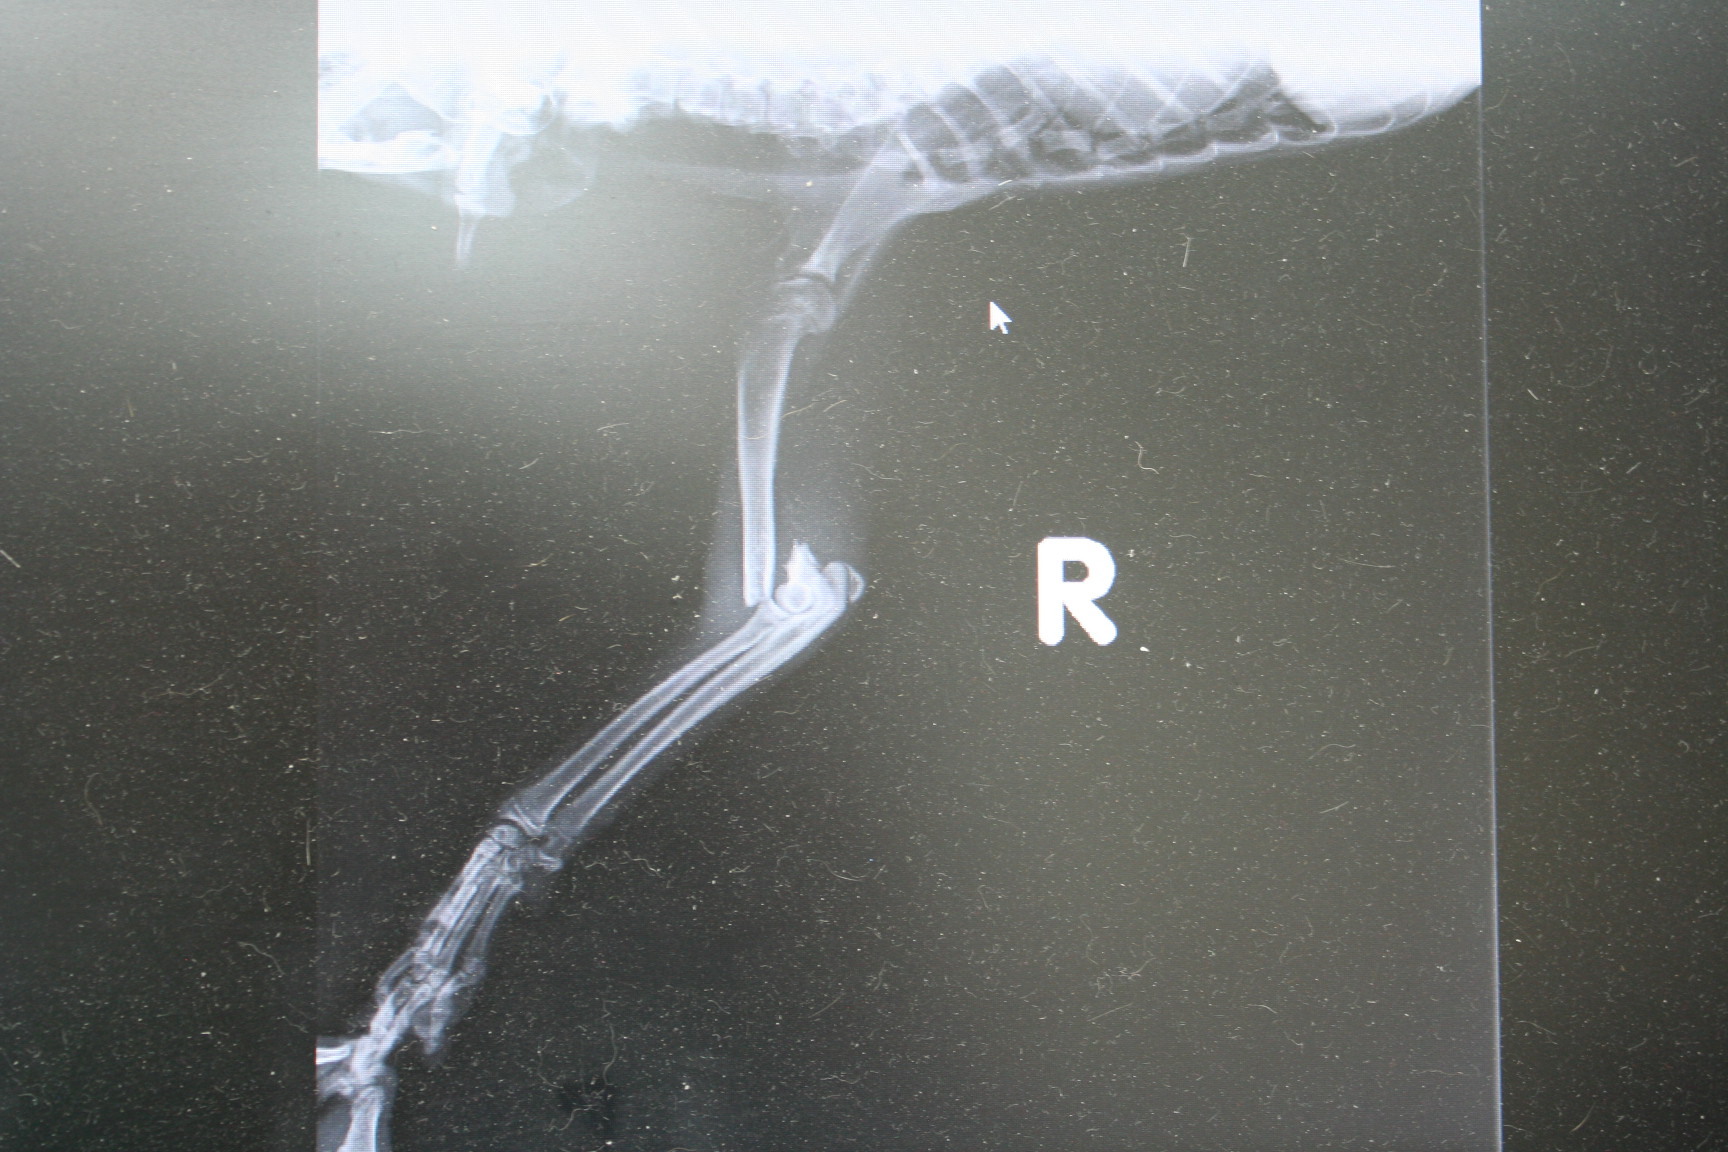

主題: 光華夜市浪浪小橘右前腿截肢 申請者姓名: Kate Vitamins 花色: 申請日期: 2013-01-01 07:31:11 申請者部落格: 申請者臉書網址: http://www.facebook.com/kate.vitamins 所在縣市/合作醫院: 高雄市/回生動物醫院 治療費用: 11610元 需求人數: 13人 已結案 (2013-02-23 14:25:59) 報名人員: okina(已付款)、游佳雯(已付款)、游佳雯(已付款)、molly(已付款)、Vronique Yang(已付款)、selina(已付款)、廖又萱(已付款)、Claudia Yang(已付款)、momo(已付款)、akari(已付款)、Lucida Chen(已付款)、papapu(已付款)、yaya(已付款)、 候補人員: 動物病情說明: 在光華夜市發現的時候跑不快,好像想靠近人又會害怕,一下就抓到了,才發現右手好像受傷的很重...附近人車又很多,好危險T^T

出院後除了拉肚子,現在很健康也很會講話,但是走路就不穩,蓋貓砂會容易踩到。

醫療明細如下

1.12/18全身血液檢查 1500

2. 12/18 二合一檢查 500

3. 12/18 傳染性腹膜炎檢查 500

4. 12/18 截肢手術 6000

5. 12/18--12/29 住院治療11X400=4400

6. 公貓結紮 另外申報

醫療費用打9折 12900 X 0.9 = 11610